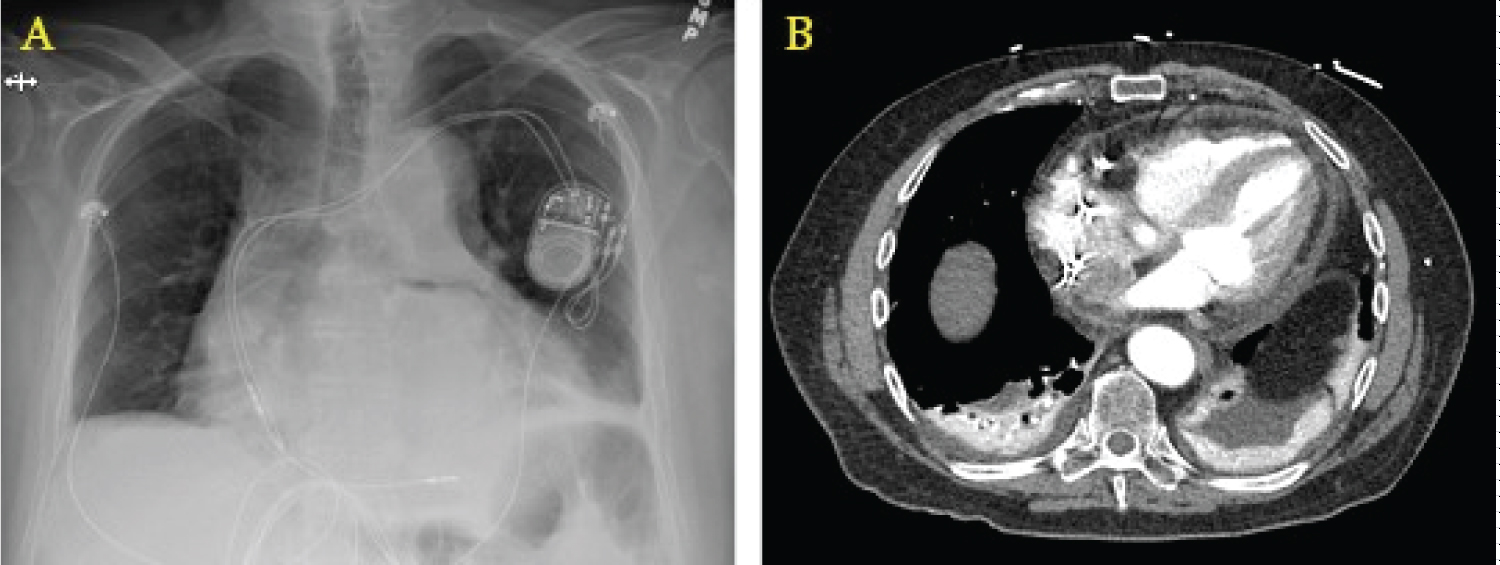

Expert-level use of intraprocedural TEE from either cardiology or anesthesia providers is crucial to success. The ability to supplement standard fluoroscopic views with real-time, multiplanar views of the anatomically complex LAA allows for a more complete map of ostium size, shape, depth, number of lobes, and position and correct sizing of devices. Per Mobius-Winkler, et al., the four ideal TEE views of the LAA include (a) A midesophageal (ME) four-chamber view at 0°, (b) A ME mitral commissural view at 60°, (c) A ME two-chamber view at 90°, and (d) A ME aortic valve long-axis view at 135°. A careful examination of each of these views should be undertaken to ensure guidewires and catheters are correctly positioned within the appendage at each step of the procedure [16]. X-plane and three-dimensional (3D) imaging can be helpful in selecting the appropriate location along the interatrial septum for the performance of transseptal puncture and guidance of wires for device delivery (Figure 1). After deployment, TEE can be used to evaluate leaking around seal devices, hemopericardium, pericardial effusion, tamponade, or right ventricular compression. Surgical treatments of AF continue to evolve. Unfortunately, the long-term prospective study results on LAA occlusion devices have been somewhat disappointing, with heterogeneous outcomes reported. The stroke prevention rate was only noninferior to oral anticoagulants, and procedures were associated with variable types of complications [15,17,18]. The recently developed Watchman FLX device has demonstrated encouraging short-term efficacy with a high degree of LAA sealing and low procedure compilation rates [19,20].

Figure 1: Schematic illustration of the guidewire punch location and direction under the direction of real-time transesophageal echocardiogram 2D/3D images. (a,b) The left atrial appendage as seen at 90° and 0°; (c) A 3D view of the wire coming across the interatrial septum; (d) A 3D image showing the wire crossing the left atrium and entering the left atrial appendage; (e) X-plane image-guidance of transseptal puncture.